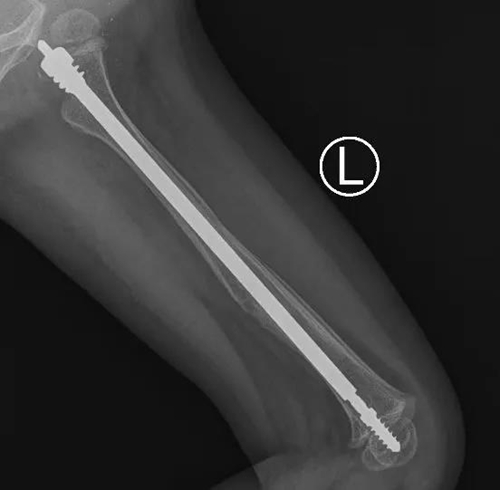

近日,青島婦女兒童醫(yī)院小兒骨科成功為一名患有“脆骨病”(又名成骨不全癥)的2歲患兒進(jìn)行了“左側(cè)股骨骨折可延長髓內(nèi)針內(nèi)固定術(shù)”治療,這是可延長式髓內(nèi)針在省內(nèi)首次應(yīng)用于“脆骨癥”患兒的骨折治療。

小兒骨科團(tuán)隊(duì)多次討論后,決定采用一種專門針對成骨不全的全新手術(shù)方式:兒童可延長式髓內(nèi)針內(nèi)固定術(shù)。這種髓內(nèi)針可以應(yīng)用于大腿、小腿、上臂等長骨骨折。隨著孩子的生長,可延長髓內(nèi)針自動滑動延長,加強(qiáng)了患兒骨質(zhì)的強(qiáng)度,減少再次骨折的幾率。

在完善各項(xiàng)檢查和準(zhǔn)備后,小兒骨科團(tuán)隊(duì)在麻醉科、手術(shù)室的配合下為彤彤進(jìn)行了微創(chuàng)手術(shù)。術(shù)中,主刀醫(yī)生小兒骨科主任董震將直徑為3.0mm的針芯和4.8mm的可延長彈性髓內(nèi)釘系統(tǒng),精準(zhǔn)的置入股骨髓腔內(nèi)完成復(fù)位和固定。手術(shù)耗時(shí)僅1.5個小時(shí),骨折部位并無手術(shù)切口,僅在遠(yuǎn)離骨折的肢體近端有個微創(chuàng)手術(shù)切口,術(shù)中出血僅5ml。目前彤彤恢復(fù)良好,已經(jīng)康復(fù)出院。